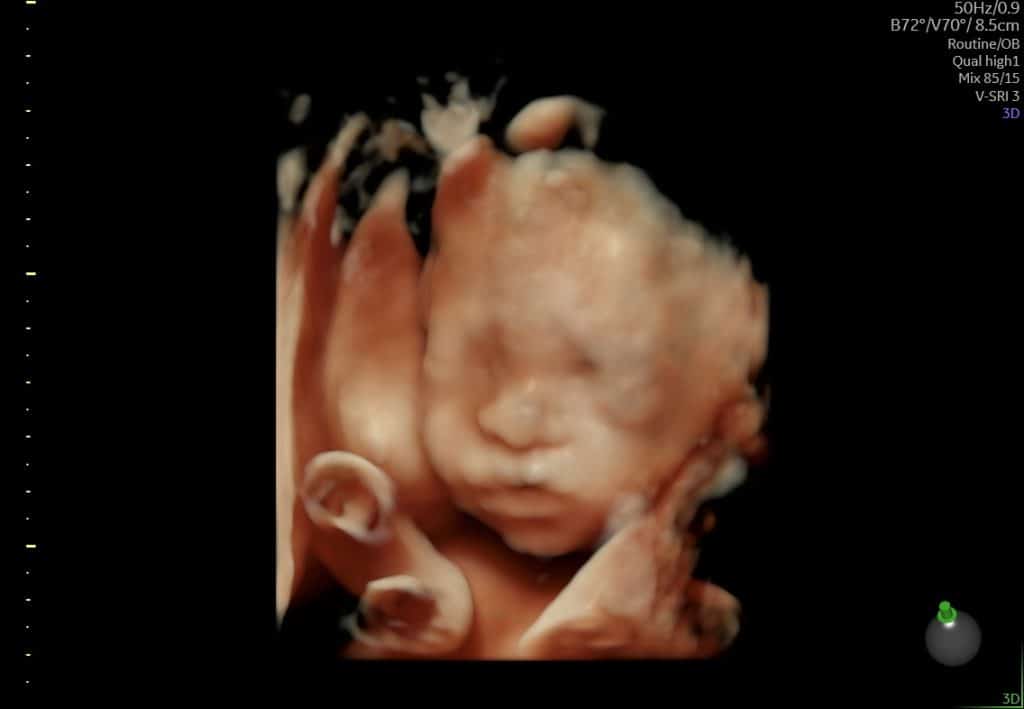

Omkring uge 26 er mange gravide særligt interesserede i 3D/4D-scanning. Her er:

- ansigtstræk mere udviklede

- kinder, næse og mund tydeligere

- mimik og bevægelser ofte synlige i 3D/4D

Betingelserne for gode 3D-billeder afhænger af barnets stilling og mængden af fostervand. Man kan ikke altid garantere bestemte billeder.

Ultralyd uge 25 baby i profil

3D-billeder kan i nogle tilfælde give et andet indtryk end 2D-ultralyd, men afhænger fortsat af barnets placering.